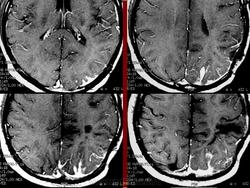

Миксоидная саркома.

1.m.slayd191.jpg2.m.slayd192.jpg3.m.slayd193.jpg4.m.slayd194.jpg5.m.slayd195.jpg6.m.slayd196.jpg7.m.slayd197.jpg8.m.slayd198.jpg9.m.slayd199.jpg10.m.slayd200.jpg11.m..slayd201.jpg12.m.slayd202.jpg13.m..slayd203.jpg